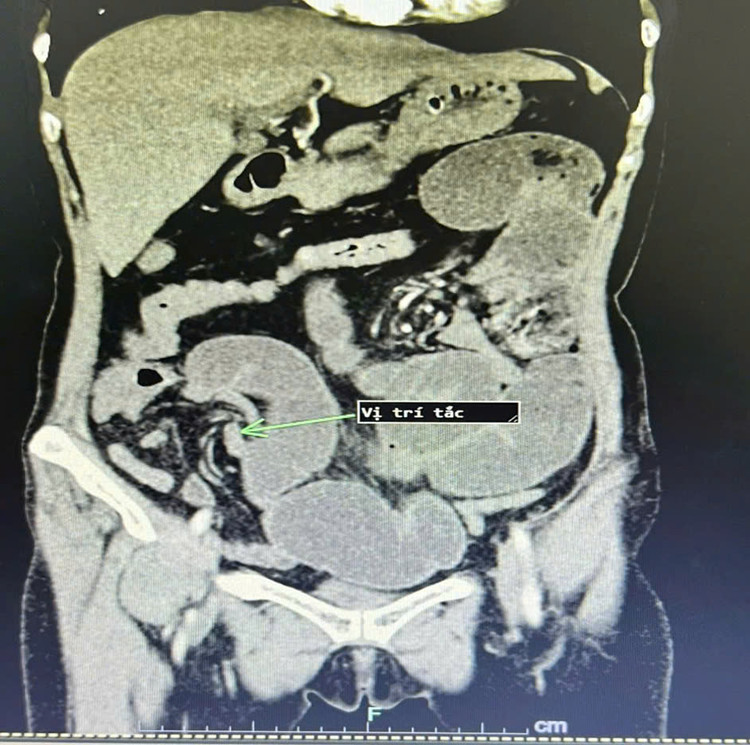

| Hình ảnh chụp cắt lớp vi tính cho thấy quai ruột tắc, giãn to khi vào viện. Ảnh BVCC |

Qua khai thác bệnh sử, người bệnh đã phẫu thuật cắt tử cung, cắt đoạn ruột non; dính ruột một lần năm 2022. Lần này, người bệnh thấy xuất hiện đau bụng kèm theo nôn gia đình đã cho nhập viện tại bệnh viện đa khoa tư nhân trên tỉnh Phú Thọ, được điều trị 10 ngày tuy nhiên không đỡ, người bệnh đã chủ động lên bệnh viện đa khoa tỉnh Phú Thọ khám.

Tại khoa Ngoại tổng hợp Bệnh viện đa khoa tỉnh Phú Thọ, người bệnh được chẩn đoán tắc ruột dính. Có chỉ định phẫu thuật gỡ dính, lập lại lưu thông ruột.

Trong mổ các BS nhận thấy các quai ruột non giãn to, dính gập góc gây tắc hoàn toàn đoạn hồi tràng gần góc hồi manh tràng. Các Bs đã tiến hành gỡ dính, cắt đoạn ruột tắc lập lại lưu thông ruột. Hiện tại, người bệnh đã ổn định và được ra viện.